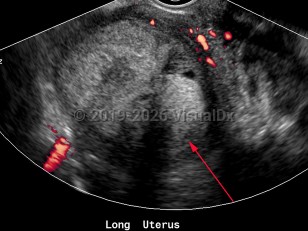

Endometrial carcinoma

Synopsis

Endometrial carcinomas are more common in White women and more likely to develop after menopause. The highest incidence worldwide is seen in the United States.

Most commonly, endometrial carcinoma develops in conditions that expose the uterus to estrogen, either for very prolonged periods of time, without opposing progesterone, or both. As such, obesity, polycystic ovarian syndrome (PCOS), diabetes mellitus type 1 and type 2, anovulation, nulliparity, tamoxifen use (in postmenopausal women), prolonged hormone replacement therapy with estrogen alone, and early menarche or late menopause are all variably potent risk factors for endometrial carcinoma.